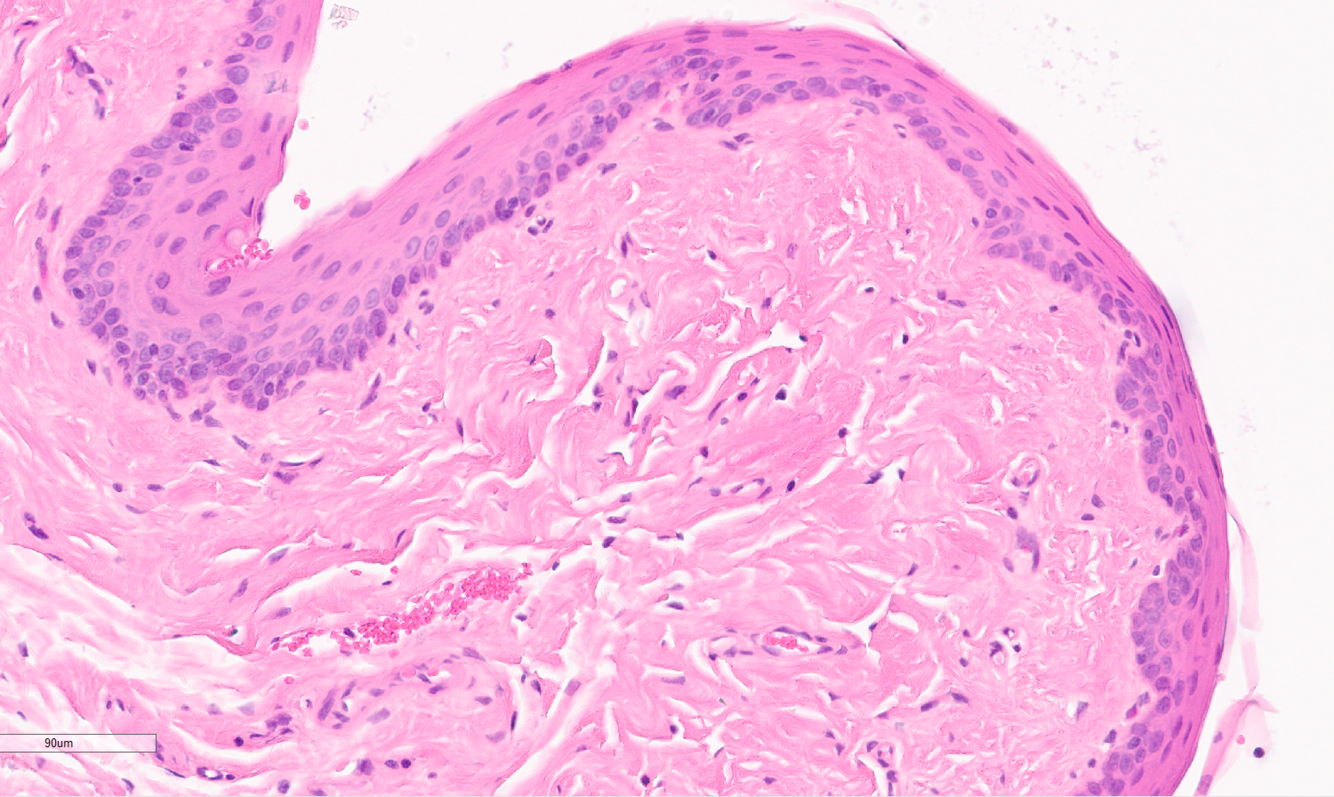

Identify this structure:

A

keratin pearl